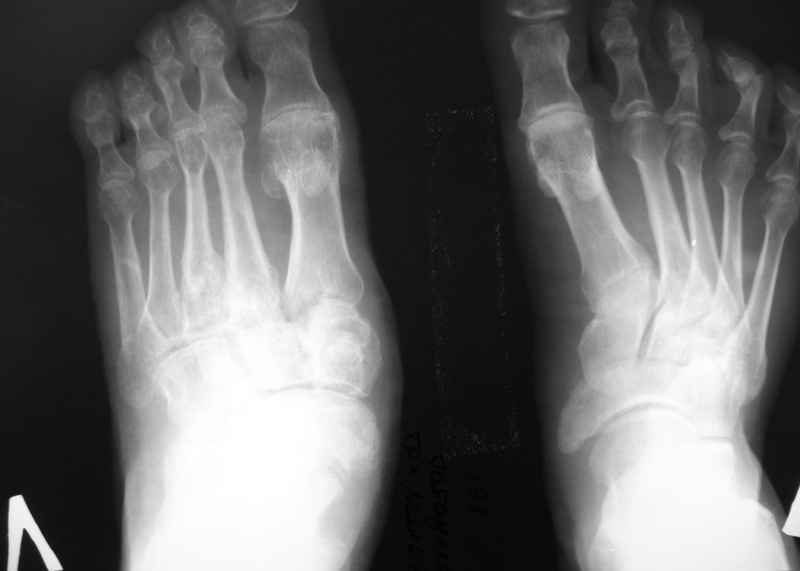

Больной с деформацией стопы Больной К., 36 лет. Травма в 2006 г.-падение с высоты. Лечился по

поводу перелома D- 12 позвонка с нижним парапарезом и оскольчатых переломов плюсневых

костей левой стопы. Производился остеосинтез переломов плюсневых костей левой стопы

спицами. В 2007 году произведена стабилизирующая операция на позвоночнике с ламинэктомией

и фиксацией металлоконструкцией и операция артродез левого голеностопного,

подтаранного, таранно-ладьевидного, межклиновидных суставов с фиксацией винтами. В 2008

г. часть винтов удалена. Больной отмечает появление парестезий и движений в пальцах обеих

стоп в этом году ( ежедневно пользуется миостимулятором Аб Троник). В настоящее время жалобы

на деформацию и нестабильность в левой стопе, боль в области голеностопного сустава, в

области пятки (проекция винта). При осмотре имеется плоско-вальгусная деформация левой

стопы, болезненность в пяточной области в проекции винта, тугоподвижность в области

шопарова сустава. На тыльной поверхности рубцы. План лечений: удаление винта с подошвенной

области, корригирующий реартродез в щопаровом суставе. Как удалить остатки винта?

Возможно понадобиться реартродез голеностопного или подтаранногосустава.

The patient with foot deformation. The patient, 36 years. Trauma in 2006 г.-falling from

height. It was treated in occasion of fractur D-12 vertebra with bottom paraparesis and

splintered fractures of metatarsal of left foot. The osteosynthesis of metatarsal bones was

made by wires. In 2007 stabilizing operation on a backbone with laminectomy and arthrodesis

of ankle,subtalar, talo-navicular, intecuneiform joints with fixing by screws . In 2008 the

part of screws is removed. The patient marks{celebrates} occurrence movements in fingers of

both stop in this year. Now patient complaints to deformation and instability in left stop, a

pain in the area of ankle joint and in the field of a heel (a projection of the screw). At survey

there is valgus and planus a deformation of left foot, morbidity in calcaneal area in a

projection of the screw,the motion in the midfoot. There are scars on a dorsal surface of foot.